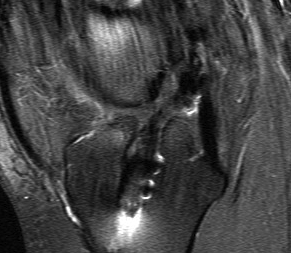

MRI

1.  Is graft intact / non functional or ruptured

Revision ACL Intact but Lax GraftRevision ACL Graft Rupture

2.  Assess meniscus / chondral surfaces

3.  Evidence of other ligament injury (difficult)